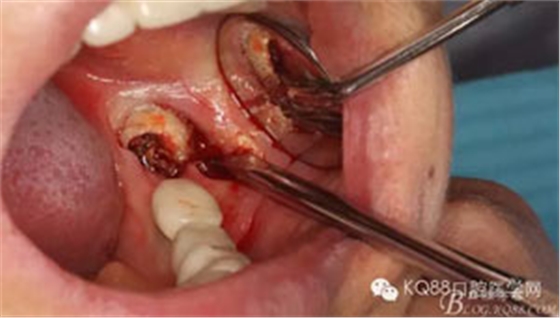

圖5.頰側(cè)做微切口、翻瓣,暴露頰側(cè)38牙體及頰側(cè)骨板。

圖6. 微創(chuàng)丫挺增隙